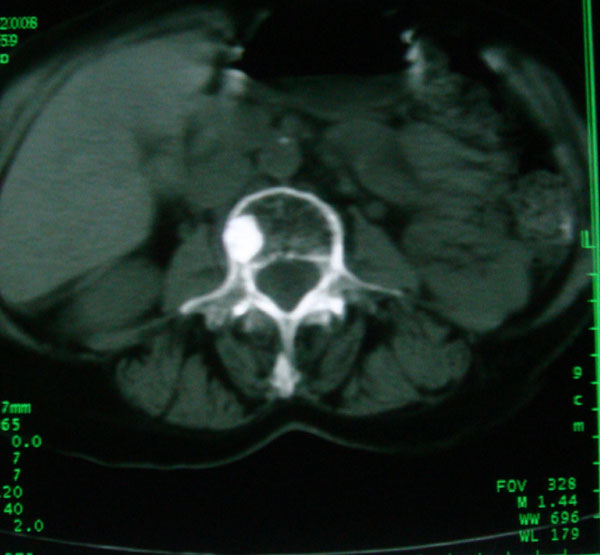

以下是引用卜一在2008-5-24 6:33:00的发言:[br]骨岛!建议定期复查!

以下是引用panyishengct在2008-5-23 23:19:00的发言:[br]骨岛,不排除成骨性转移瘤.

以下是引用pujunzhi在2008-5-24 1:02:00的发言:[br]支持2楼 骨岛,不排除成骨性转移瘤

以下是引用gaoshengjiang在2008-5-24 8:25:00的发言:[br]骨岛,不排除成骨性转移瘤. [br] [br]

以下是引用zjzjr在2008-5-24 14:55:00的发言:[br]骨岛!建议定期复查!